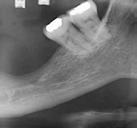

Este caso clínico es un premolar que tiene 3 conductos: sabemos que 2 de ellos son en la raíz vestibular, y

en el CBCT podemos apreciar a qué longitud del conducto se produce la bifurcación (Figura 10)

Figura 10. Estudio Radiográfico en 2D y 3D del caso clínico. Figura 11. Secuencia operatoria que realizamos en cada uno de los conductos. Figura 12. Secuencia realizada para la obturación con onda continua.